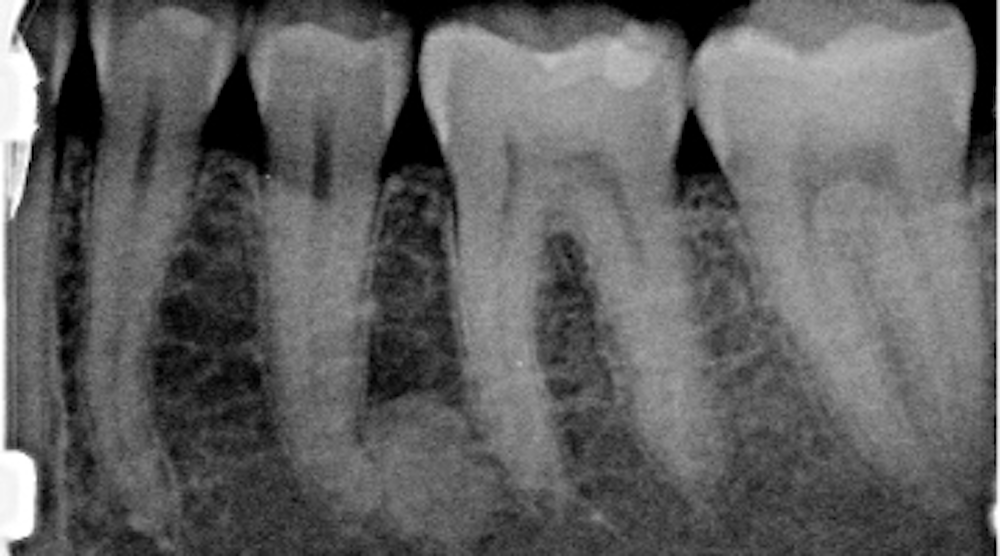

Condensing Osteitis X Ray . Condensing osteitis (periapical sclerosis osteitis or focal sclerosing osteitis): Condensing osteitis or focal sclerosing osteitis is a periapical inflammatory condition. However, imaging characteristics can deviate according to the evolution of the lesion, and cod can be mistaken for a periapical inflammatory lesion at early stages ( 16 ). Note that both the crowns. Condensing osteitis is a dental condition that manifests as a bony radiopacity (observed radiographically), usually in the lower. Mandibular left molar pa radiograph showing condensing osteitis in relation to both first and second molar roots. Condensing osteitis is a periapical inflammatory disease that results from a reaction to a dental related infection. The disease often impacts the bone next to teeth that have undergone endodontic therapy or restored with other techniques. Occurs due to chronic inflammation and is often. Dentists notice abnormal bone growth and lesions in affected molars on the jawbone. A narrow radiolucent halo distinguishes cod from condensing osteitis and idiopathic osteosclerosis.

A narrow radiolucent halo distinguishes cod from condensing osteitis and idiopathic osteosclerosis. The disease often impacts the bone next to teeth that have undergone endodontic therapy or restored with other techniques. Condensing osteitis or focal sclerosing osteitis is a periapical inflammatory condition. Condensing osteitis is a dental condition that manifests as a bony radiopacity (observed radiographically), usually in the lower. Condensing osteitis (periapical sclerosis osteitis or focal sclerosing osteitis): Dentists notice abnormal bone growth and lesions in affected molars on the jawbone. Occurs due to chronic inflammation and is often. Mandibular left molar pa radiograph showing condensing osteitis in relation to both first and second molar roots. Note that both the crowns. Condensing osteitis is a periapical inflammatory disease that results from a reaction to a dental related infection.